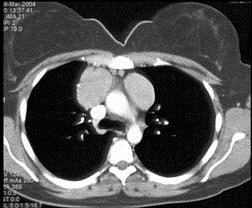

问题 女,27岁,双侧颈部淋巴结肿大,PPD(-),请结合CT图像,选择最可能的诊断 ( )

选项 A.心包囊肿 B.淋巴瘤 C.淋巴结核 D.转移性淋巴结肿大 E.结节病

答案 B